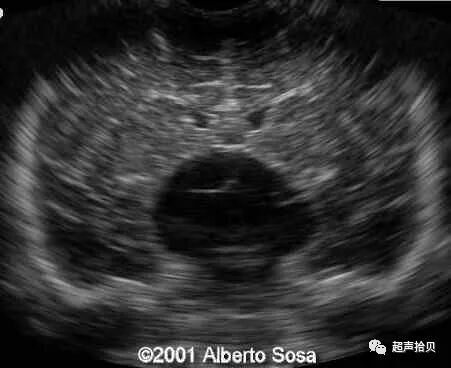

图1:横向声像图显示位于中线蛛网膜囊肿(C), 彩色多普勒没有血流显示;